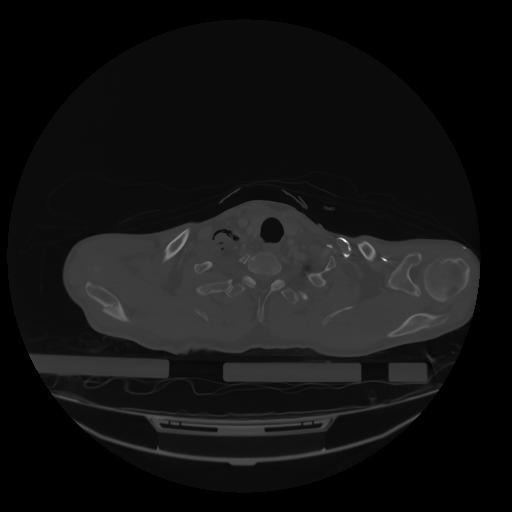

28 CUERPO,CE,Vol,2.0,CUERPO,,